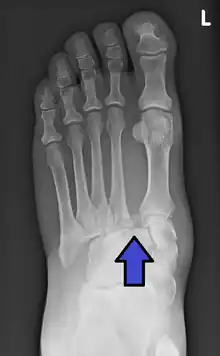

An X-ray of a Lisfranc injury

Lisfranc fracture (marked by the oval). This case also has fractures of the distal second (marked by the arrow), third, and fourth metatarsal bones.

In a high energy injury to the midfoot, such as a fall from a height or a motor vehicle accident, the diagnosis of a Lisfranc injury should, in theory at least, pose less of a challenge. There will be deformity of the midfoot and X-ray abnormalities should be obvious. Further, the nature of the injury will create heightened clinical suspicion and there may even be disruption of the overlying skin and compromise of the blood supply. Typical X-ray findings would include a gap between the base of the first and second toes.[8] The diagnosis becomes more challenging in the case of low energy incidents, such as might occur with a twisting injury on the racquetball court, or when an American Football lineman is forced back upon a foot that is already in a fully plantar flexed position. Then, there may only be complaint of inability to bear weight and some mild swelling of the forefoot or midfoot. Bruising of the arch has been described as diagnostic in these circumstances but may well be absent.[9] Typically, conventional radiography of the foot is utilized with standard non-weight bearing views, supplemented by weight bearing views which may demonstrate widening of the interval between the first and second toes, if the initial views fail to show abnormality. Unfortunately, radiographs in such circumstances have a sensitivity of 50% when non-weight bearing and 85% when weight bearing, meaning that they will appear normal in 15% of cases where a Lisfranc injury actually exists.[10] In the case of apparently normal x-rays, if clinical suspicion remains, advanced imaging such as magnetic resonance imaging (MRI) or computed tomography (CT scan) is a logical next step.[11]